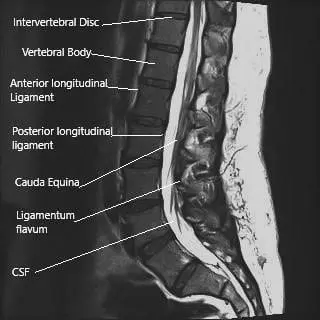

MRI of the lumbosacral spine in sagittal section.

The spinal cord ends at the level of lower L1/L2 vertebrae. The spinal cord continues below as a collection of spinal nerve roots that branch from their respective neural foramen. The spinal cord and the bunch of spinal nerves (cauda equina) are covered by a protective covering known as dura mater.

The epidural corticosteroid injections are aimed to be delivered just outside the dura mater (epidural space). The epidural space contains the exiting nerve roots, dural sac, blood vessels, and fat. The epidural corticosteroid injections provide a localized concentration of steroid.